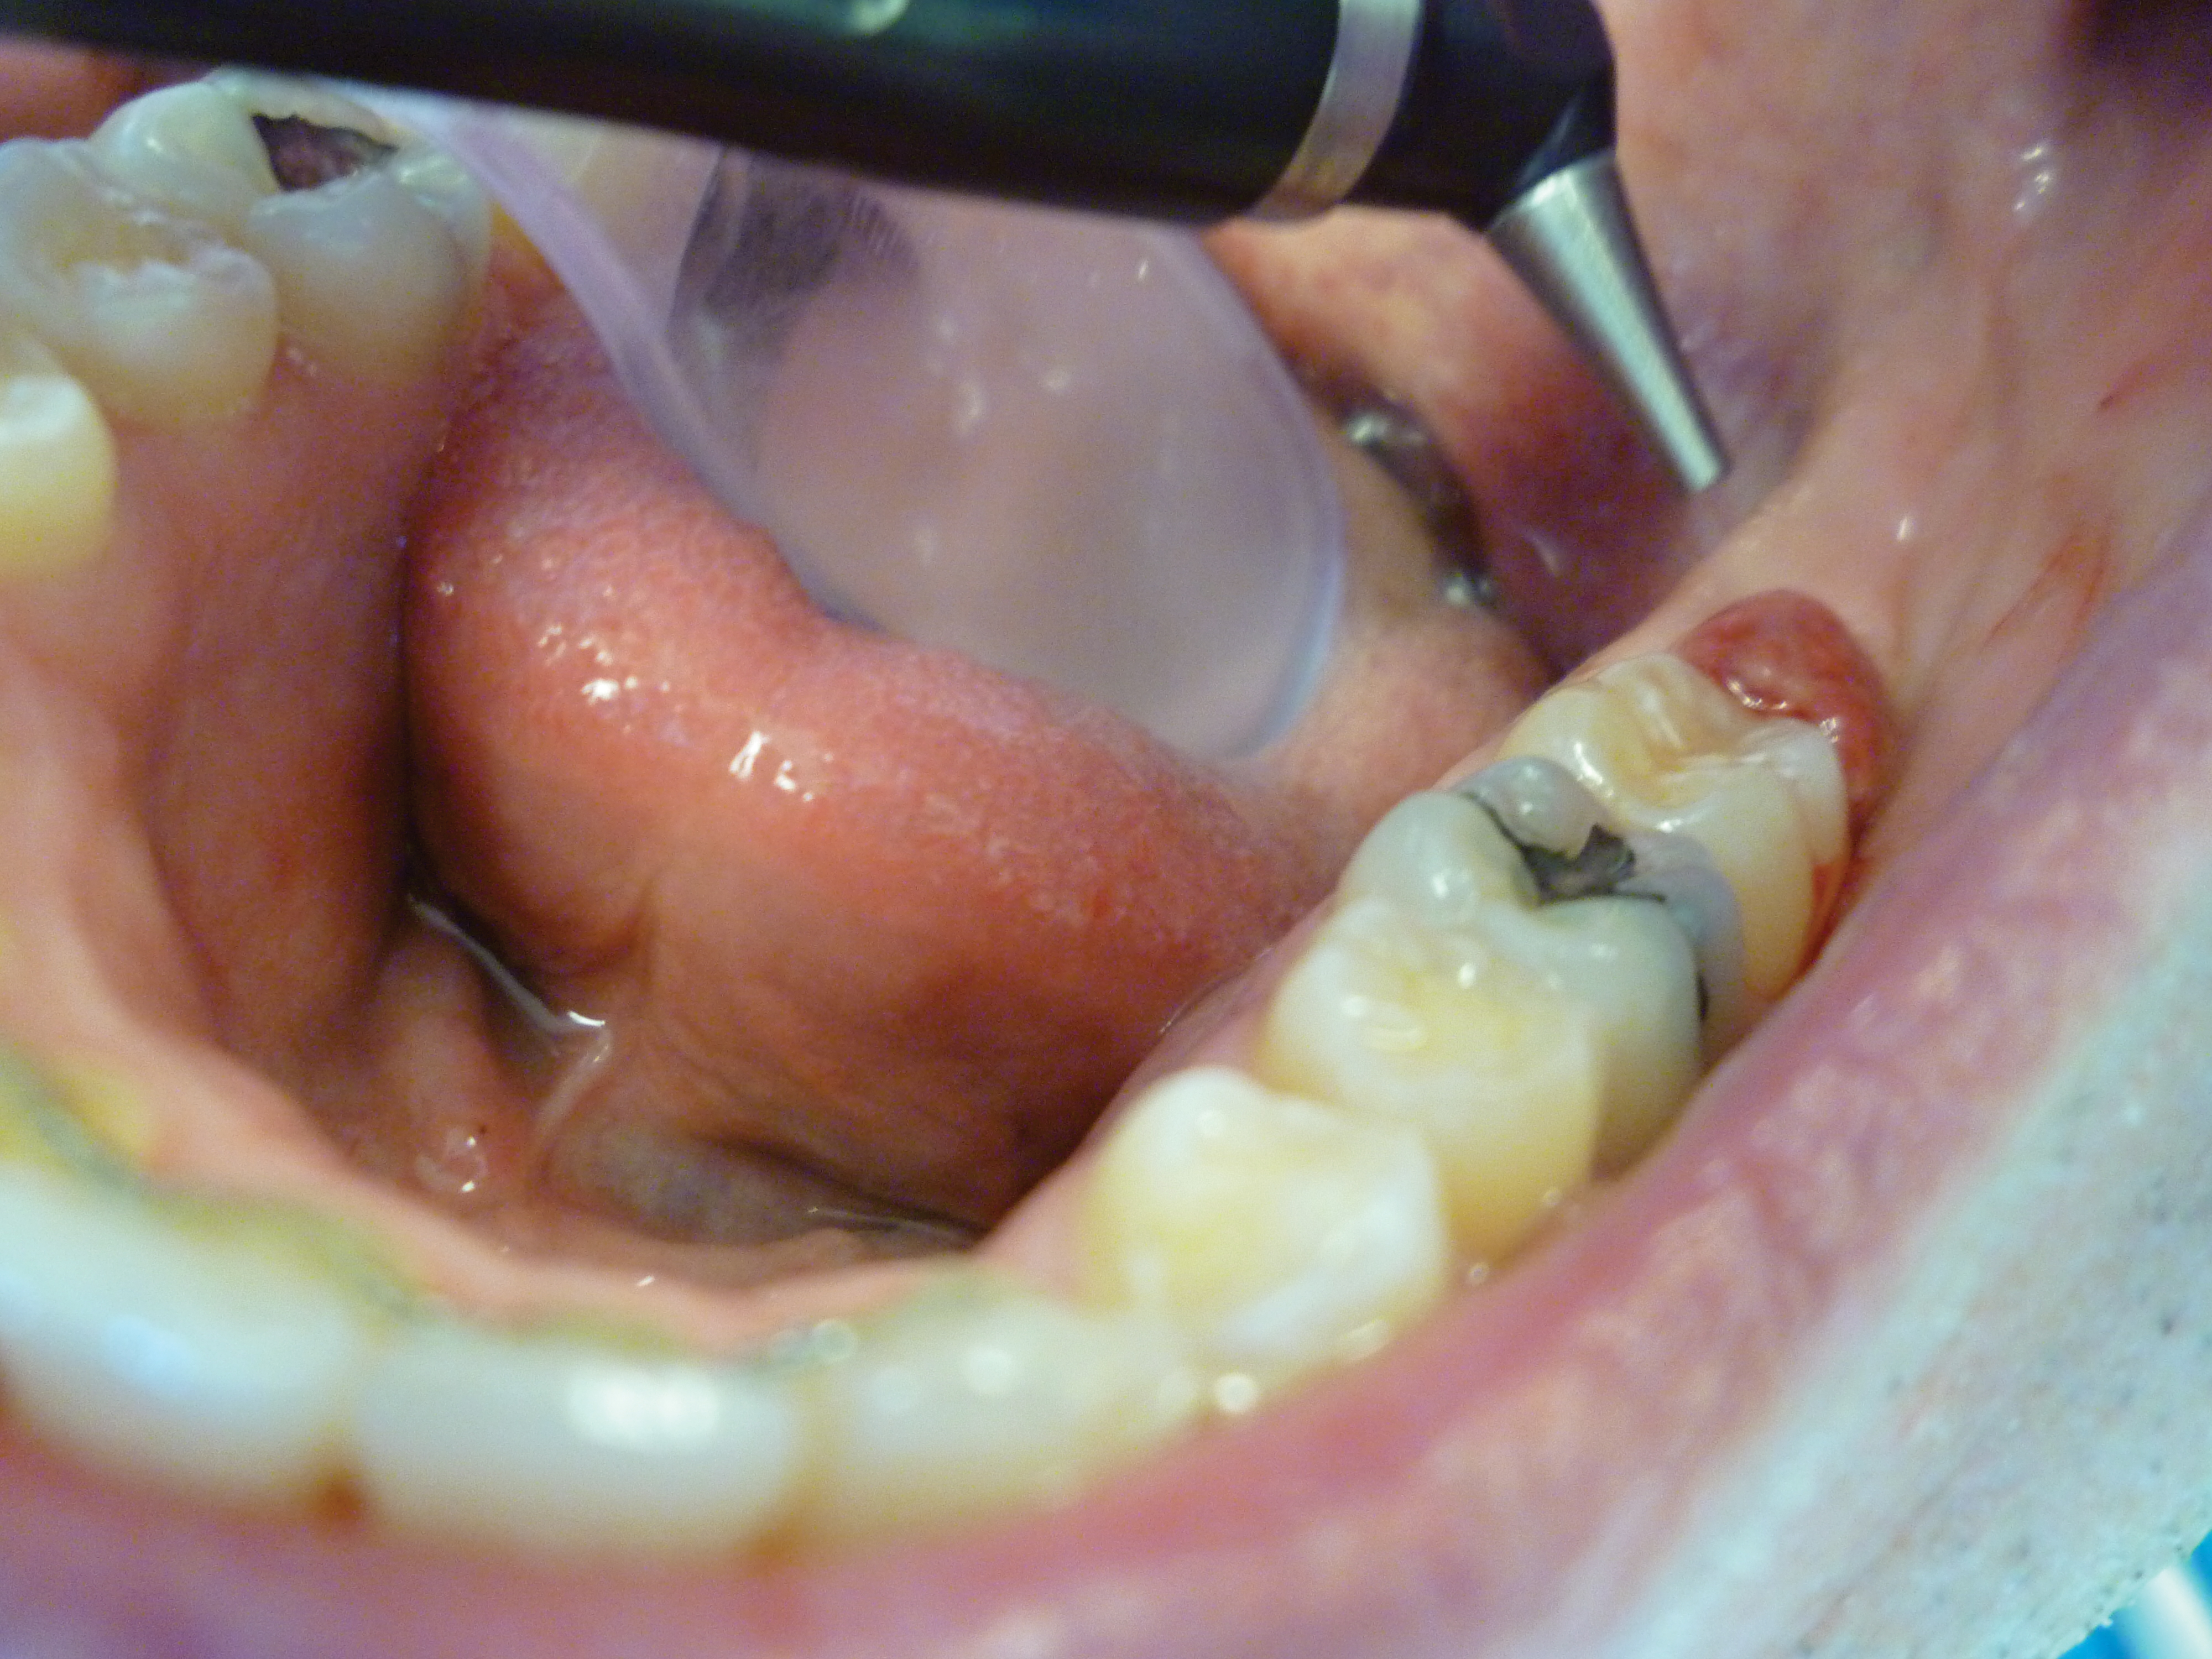

Operculectomy by CO2 Laser Ablation: Case Study Initial Findings

The patient presented with a raised, inflamed, painful operculum distal to the left mandibular second molar (Figure 3). The lesion was red, edematous, and bled easily. A periodontal pocket on the distal of the second molar was >6 mm deep. There was no evidence of abscess.

Fig 3. Preoperative view of the inflamed operculum.

Figure 3